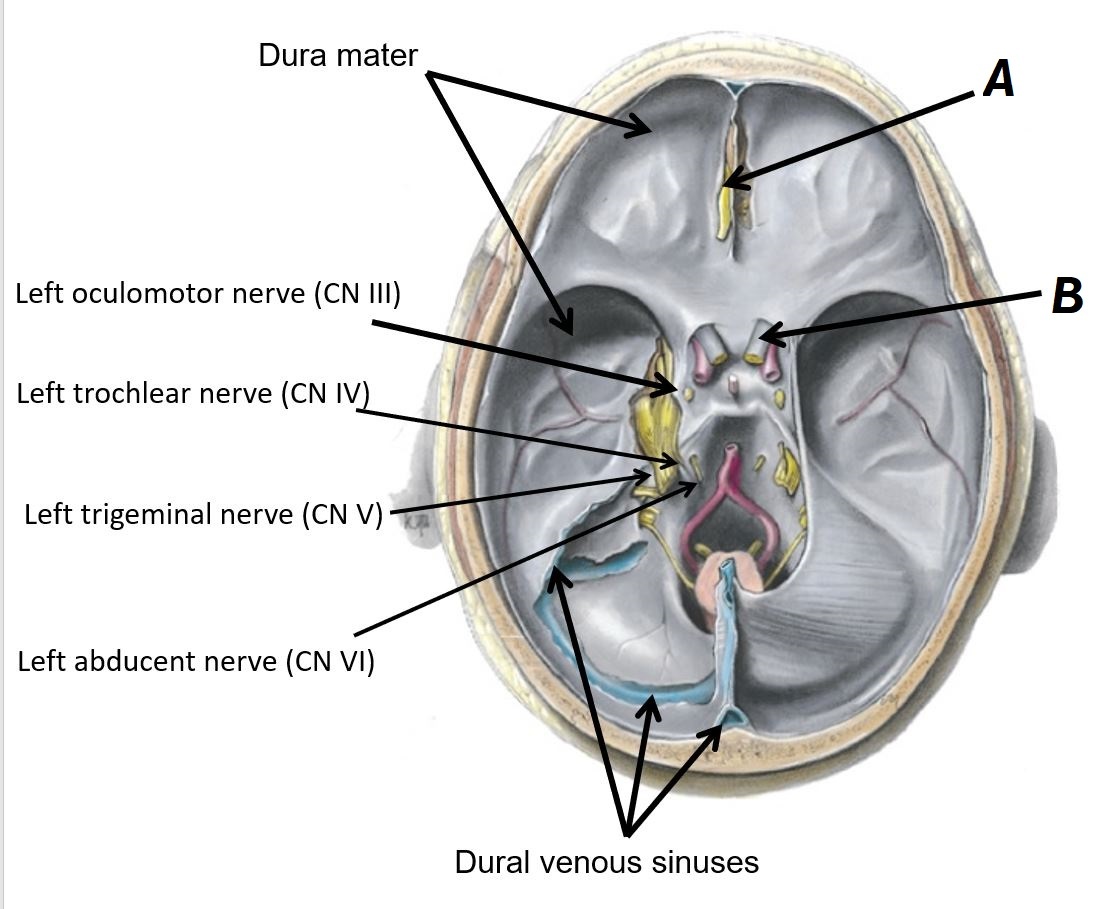

Name nerves A to D

A - Oculomotor nerve (CN III)

B - Trochlear nerve (CN IV)

C - Trigeminal nerve (CN V)

D - Abducens nerve (CN VI)

Name nerves A and B

A - Left olfactory nerve (CN I)

B - Right optic nerve (CN II)

Name structures A and B

A - Dura mater

B - Dural venous sinuses